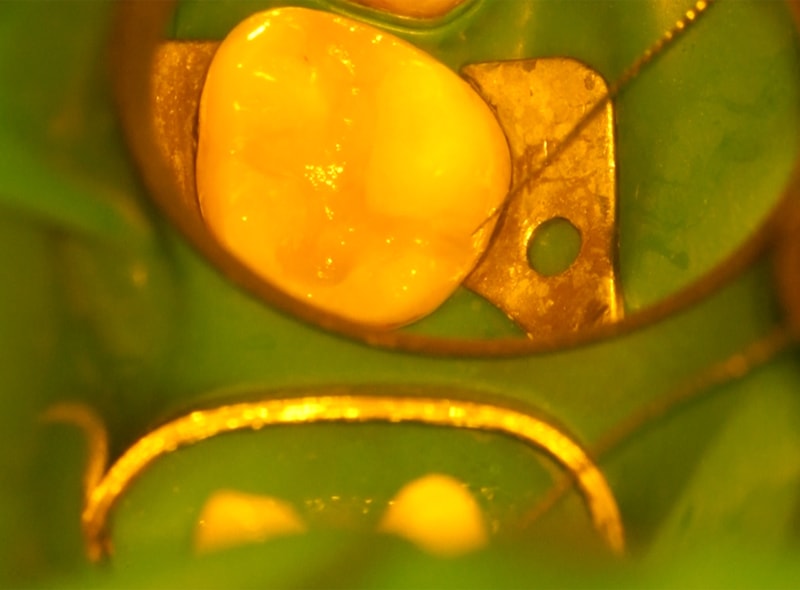

マイクロスコープによる精密な治療

当院では、肉眼では確認しにくい歯の細部までしっかりと拡大して見ることができる「マイクロスコープ」を用いて治療を行っています。これにより、虫歯の取り残しを防ぎ、健康な部分を必要以上に削らずに済むよう配慮しています。従来の治療よりも正確で丁寧な処置が可能になるため、歯の寿命をのばし、将来にわたってご自身の歯をできるだけ長く保つことにつながります。小さな虫歯でも見逃さず、一つひとつ丁寧に対応することで、患者さんに安心して治療を受けていただける環境を整えています。

マイクロスコープを使えば最大25倍まで視野を拡大でき、虫歯の取り残しや髪の毛ほどの亀裂、根管内の見落としを防げます。

当院では虫歯治療、根管治療、審美修復などにマイクロスコープを取り入れ、「見て確認しながら進める治療」を徹底しています。